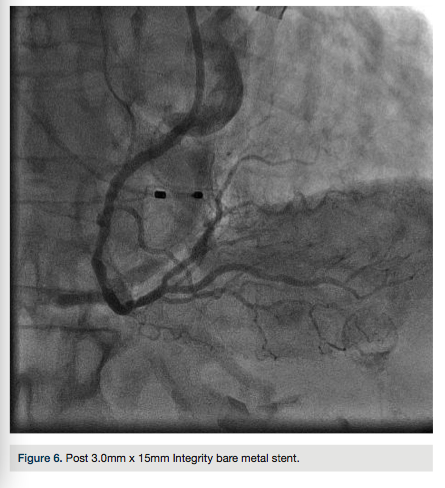

An 84-year-old female with a history of hypertension, diabetes, and dyslipidemia presented to the emergency department with approximately one hour of chest pain and dizziness. Initial electrocardiogram (EKG) demonstrated ST elevations with complete heart block (Figure 1). She was brought to the lab for emergent cardiac catheterization. Diagnostic angiography and percutaneous coronary intervention (PCI) were performed via the right radial artery. A transvenous pacemaker was inserted from the right antecubital vein.

The right radial artery was prepped and draped in sterile fashion, then accessed with a 6 French (Fr) Glidesheath (Terumo). The right antecubital vein was accessed by the nurse prior to the patient’s arrival to the lab and changed (after sterile prep followed by betadine solution) to a 5 Fr Glidesheath (Figure 2). The transvenous pacemaker was advanced  into the right ventricle (Figure 3). Following placement of the pacemaker and capture, a Judkins right (JR) 4 6 Fr guide was used to engage the right coronary artery. Angiography demonstrated a proximal right coronary artery occlusion with TIMI-0 flow (Figure 4). After administration of bivalirudin (Angiomax, The Medicines Company), a Runthrough wire (Terumo) was passed distally. A 1.0 x 10 mm ClearWay balloon (Atrium Medical) was advanced to the lesion and intracoronary abciximab (ReoPro, Eli Lilly & Co.) was administered. Following drug administration, there was improved flow and evidence of a more focal obstruction (Figure 5). A 3.0 x 15 mm Integrity bare metal stent (Medtronic) was deployed at 11 atm with no angiographic residual stenosis and restoration of TIMI-3 flow (Figure 6).  Following revascularization of the right coronary artery, the guide was advanced into the left ventricle to calculate the left ventricular end diastolic pressure (LVEDP) and perform ventriculography (estimated ejection fraction was 55% with mild inferobasal hypokinesis noted on hand injection.  No significant transvalvular gradient was noted on pull-back). A diagnostic Judkins left (JL) 3.5 catheter was then used to engage the left coronary system. Angiography revealed a 90% proximal left anterior descending coronary artery (LAD) stenosis and intermediate disease of the circumflex (Figure 7).  The patient was started on ticagrelor (Brilinta, AstraZeneca) and aspirin, and transferred to the unit. The pacemaker was removed after the patient regained sinus rhythm. She was discharged home after 48 hours with plans for staged intervention of the LAD.